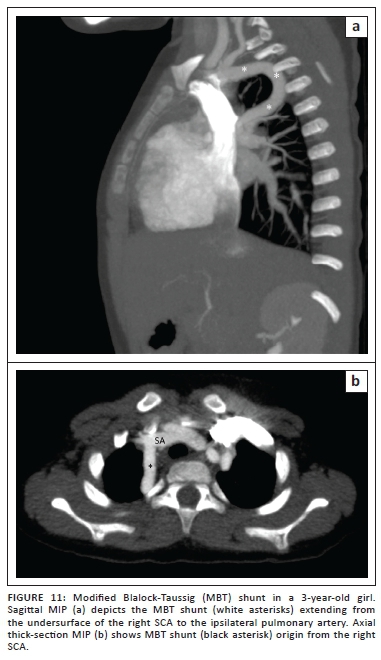

Systemic to pulmonary artery shunting procedures are well recognised interim surgical interventions, performed to augment pulmonary bloodflow prior to definitive corrective repair, to improve cyanosis, symptoms and general quality of life. Despite the trend towards single reparative operations, physiological and anatomical conditions (hypoplastic pulmonary arteries, coronary anomalies crossing the RVOT, avoidance of a conduit in a small RVOT) may preclude early definitive repair. Several types of palliative shunts have been described since the classic Blalock-Taussig (CBT) procedure of 1945, many of which have fallen out of favour (such as Potts and Waterston shunts) owing to subsequent pulmonary hypertension.

The modified Blalock-Taussig (MBT) shunt (Figure 11) directs blood from the subclavian artery opposite the aortic arch to the pulmonary artery via a PTFE or Goretex conduit graft rather than an end-to-side anastomosis of the ligated and divided native subclavian artery of the CBT shunt. Improved patency rates and ease of subsequent closure, favour the use of these shunts in our institution.

Central shunts using PTFE interposed between the ascending aorta and the main pulmonary artery are also in use. Where echocardiography may be challenging, CTA is once again perfectly suited to establish shunt anatomy and patency (Figure 12).

Pulmonary artery distortion owing to previous palliative shunting in older children lost to follow-up is elegantly displayed at CTA as an alternative to invasive angiography.